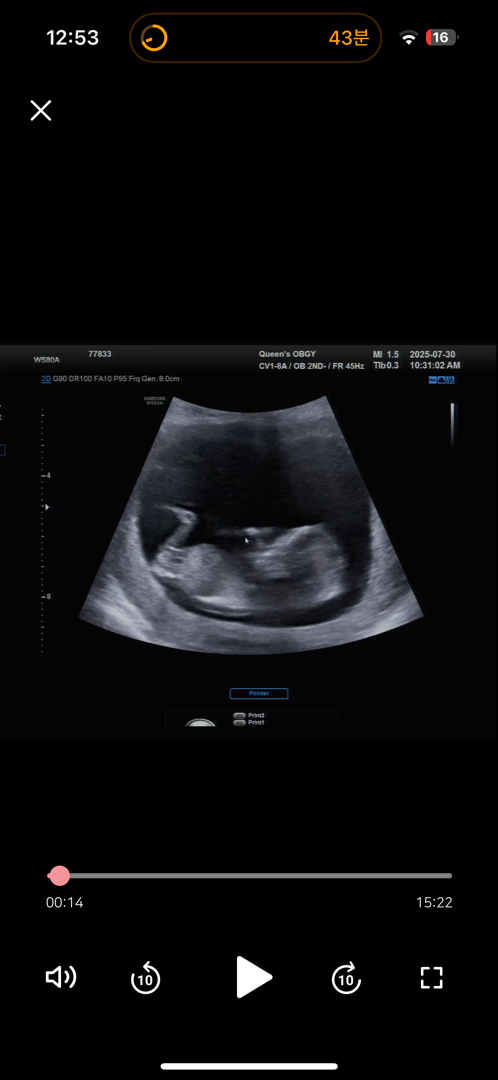

딸인가요 아들인가요…? 생식기는 안보이는거같아요ㅠ